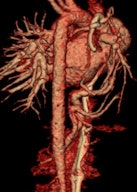

MDCT using a low radiation dose protocol is the best diagnostic tool for assessing the central airway, cardiovascular and mediastinal abnormalities, and the lung parenchyma in children, and the relevant information can be acquired with a single-volumetric data set acquisition, she stated. Using thin-slice collimation acquisition with inherent isotropic resolution, the image data can be manipulated and reformatted to display 2D and 3D images with the same spatial resolution as the axial images, thus enhancing diagnostic accuracy and providing data that can be used in presurgical planning and patient management.